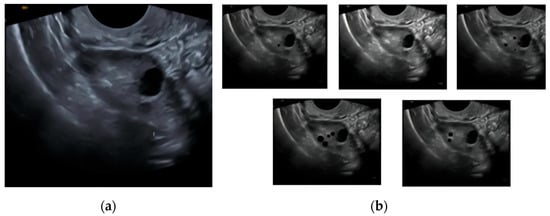

The CNN model uses ultrasound transvaginal scans for around 250 synthetically generated cases under 5 classes divided on the basis of ovarian function (Figure 1). The classes are active, inactive, declining, perimenopausal, and anomalous [9]. There are around 50 cases for each case in order to simulate realistic transvaginal ultrasound scans and make sure that the model learns most visual features of the various ovarian functionality classes.

Figure 1.

Demonstration of synthetic dataset creation: (a) base transvaginal image used for synthesis; (b) derived class images (active, inactive, declining, perimenopausal, and anomalous).